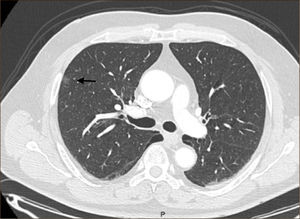

El diagnóstico por imágenes mediante TAC de Tórax, cumple por tanto un rol fundamental en la identificación y caracterización de los nódulos pulmonares. Los cánceres pulmonares iniciales pueden presentarse como nódulos de diferente densidad: sólidos, cavitados, en vidrio esmerilado (VE: definidas como una intensidad discretamente mayor a la del parénquima pulmonar a través de la cual la vasculatura pulmonar es visible) o lesiones mixtas con componente sólido y VE. Figuras 2 y 33. En etapas más avanzadas los CPNCP se presentan como nódulos de mayor tamaño o masas (>3cms), sin embargo también pueden presentarse como lesiones consolidadas mal definidas, especialmente algunos adenocarcinomas productores de mucina. Estas lesiones pueden ser indistinguibles de una neumonía, pero a diferencia de estas persisten en el tiempo pese al tratamiento antibiótico 27,28.

Sólo un bajo número de los NP corresponden a cánceres pulmonares 3,38. En el estudio ELCAP 2,7% y en NLST a 3.8% de los nódulos pesquisados correspondieron finalmente a un CPNCP 21,23,38. Las principales características radiológicas que ayudan a diferenciar un nódulo maligno de uno benigno son: tamaño, densidad y refuerzo con el medio de contraste, además son útiles el contorno del borde, forma, calcificaciones, contenido graso y cavitaciones 3,39.

Los NP con bordes irregulares, espiculados, lobulados o mal definidos tienen una mayor probabilidad de malignidad 40–42. Los CPNCP tienen una mayor vasculatura que los nódulos benignos40. Al evaluar un nódulo en un TAC sin contraste inicial y compararlo luego de la administración de medio de contraste endovenoso se puede evaluar el cambio de densidad, medido en Unidades Hounsfield (UH). Un incremento de menos de 15UH es muy sugerente de benignidad, con una sensibilidad de 98%43,44. Por el contrario un aumento de más de 15UH es sugerente de malignidad. Usando como punto de corte 30UH el valor predictivo positivo de que el nódulo sea maligno alcanza un 71%40,43.

En relación al tamaño mientras mayor sea el tamaño del nódulo mayor es su riesgo de malignidad. Los nódulos menores de 5mm tienen un riesgo de malignidad de 1%, entre 6 a 10mm 24% y entre 11 y 20mm aumenta a 33%. Los nódulos sólidos mayores de 20mm tienen un riesgo de malignidad de 80% y los mayores de 30mm de 90%45–47.

Las lesiones Subsólidas tienen un mayor riesgo de malignidad que puede alcanzar un 18%51. Las lesiones subsólidas pueden corresponder a lesiones en Vidrio Esmerilado Puro (VE o GGO: Ground Glass Opacity) o a lesiones mixtas con un componente en VE y una zona sólida (Figuras 4, 5 y 6).